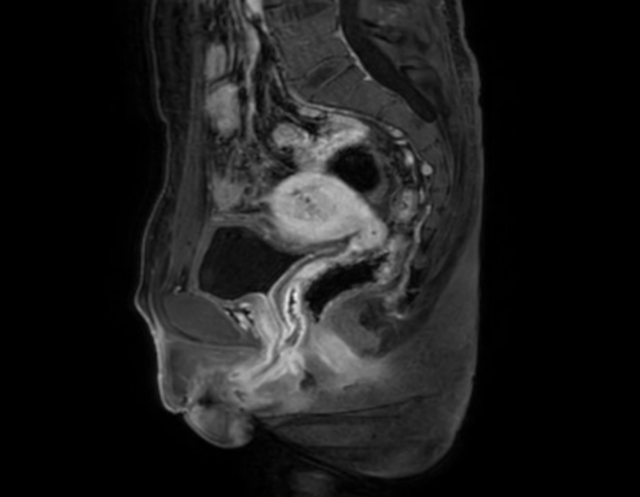

罗喜平先容,患者的子宫大部分位于腹膜外,小部分位于腹膜内,女性生殖器官剖解位置变异复杂,大大增多了手术的难度。手术分为系列调治,手法需要尤为考究。行家们为陈立量身定制了调治决策。

6月6日,手术启动。陈立给与了腹腔镜下右侧卵巢切除术、盆腔结节切除术、腹腔镜转开腹全子宫切除术、外阴结节活检术、腹腔镜下盆腔粘连松解术、腹腔镜下肠粘连松解术等系列手术,透顶切除女性生殖器官。